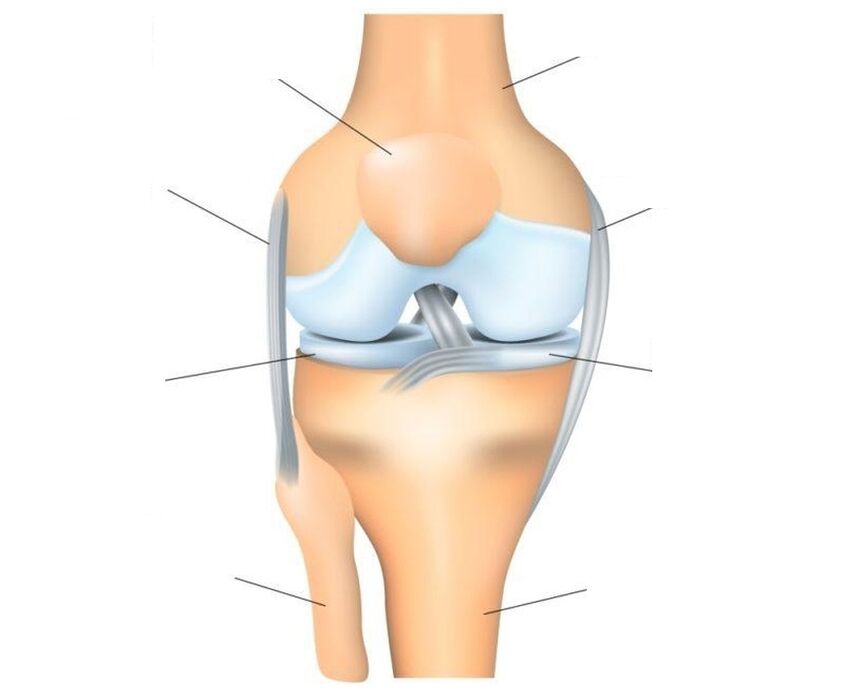

Belauneko artikulazioa da artikulaziorik konplexuena, karga nagusia jasaten baitu. Egitura: hiru hezur (femura, tibia eta rotula giltzadura troklear bakarra osatzen dute, elkarri lotuta dauden bi artikulazioz osatua: femorotibiala (tibiofemorala) eta femoro-patellofemorala (patellofemorala).

Rotula hezur sesamoide laua da (giltzaduran gehigarria), femurraren buruari lotuta dagoena, bere zirrikitu ahurran irristatuz eta bloke gisa jokatzen duena. Egiturazko ezaugarriak: patelaren aurreko gainazala periostioz estalita dago, atzeko gainazala, femurarekin lotzen duena, kartilago hialinoz estalita dago. Rotula lotailuek indartzen dute: nagusia eta albokoa - bertikala (goikoa eta behekoa) eta horizontala (albokoa - barnekoa eta kanpokoa).

O koadrizeps femoris muskuluaren indarra beheko hankaren formazio muskuloskeletikoetara transmititzen du, beheko hankaren hedapena bermatuz belauneko artikulazioan. Artikulazioak osatzen dituzten hezurren gainazala kartilagoz estalita dago, kolpeak xurgatzaile gisa jarduten duena. Artikulazioa lesioetatik babesten duten kolpe xurgatzaile gehigarriak femurra eta tibia artean kokatutako ilargierdi itxurako bi menisko kartilaginoso dira. Lotailuek, tendoiek eta inguruko kapsulek posizio egokian mantentzen dute artikulazioa.

Lesioek eta gaixotasunek hainbat ehun artikulazio eragiten dute. Denak ezin dira gaixotu. Horrela, kartilago-ehunak ez du nerbio-amaierarik eta, beraz, oharkabean eta minik gabe suntsitu daiteke. Baina lotailuek eta mintz sinobialek nerbio-bukaera asko dituzte eta lesioen edo hanturazko prozesuen kasuan berehala hasten dira erreakzionatzen, eta horrek min larria adierazten du. Artikularraren kartilagoaren suntsipen nabarmenarekin, mina periostioaren inplikazioarekin lotu daiteke, inerbazio ona duen kanpoko hezur-geruza, prozesuan.